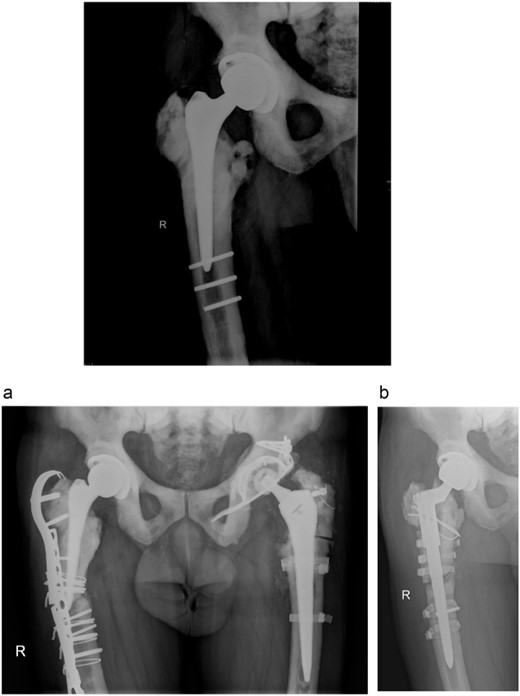

In 2011, a cementless THA of the right hip was done for the osteoarthritis. Three residual broken screws were present in the distal diaphysis from previous surgeries and were left in place (Fig. 3).

Anteroposterior radiograph of the right hip after THA with three broken residual screws in the distal diaphysis. (a) Anteroposterior hip radiograph with broken lateral plate. (b) Anteroposterior radiograph of the right hip after exchanging the femoral stem.

In 2013, the patient suffered a spontaneous Vancouver B2 periprosthetic fracture of the right THA. Osteosynthesis with a locking plate with screws and cerclages was done. Three months after the surgery, the plate broke and was exchanged with addition of an anterior plate and autologous spongioplasty. However, osteosynthesis failed 8 months later and the firmly ingrown femoral component was revised (Fig. 3a). Proximal femoral osteotomy resulted in several broken fragments. During removal of the broken screws, three sets of removal instruments were destroyed. A cementless revision modular stem was inserted and bone fragments fixed with cerclage wires and titanium tapes (Fig. 3b). Surgery took 6 h and he received six units of blood. Microbiological tissue samples were negative.